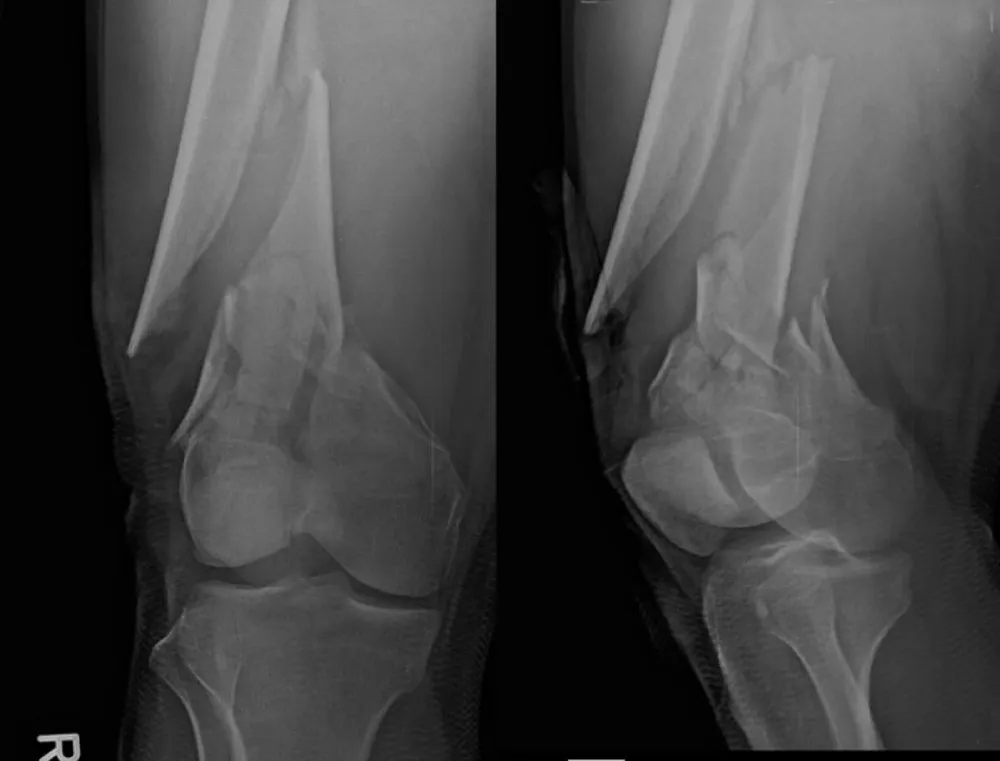

Figure 2: Pre-operative imaging of distal femur fractures. Representative lateral views demonstrate bilateral open distal femur fractures (right Gustilo‑Anderson II; left I).

Figure 3: Additional pre-operative oblique/lateral projections detailing comminution and distal extension.